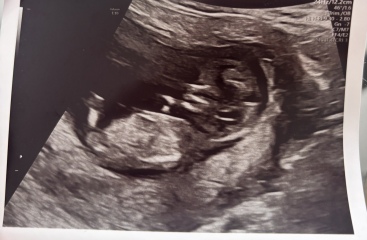

I went for my 12 week scan yesterday and curious what everyone thinks the gender of my baby is based on the nub theory, I’m not even sure if you can see what you need to see from these scans?!😅baby was measuring 12 weeks exactly!

Thank you ☺️